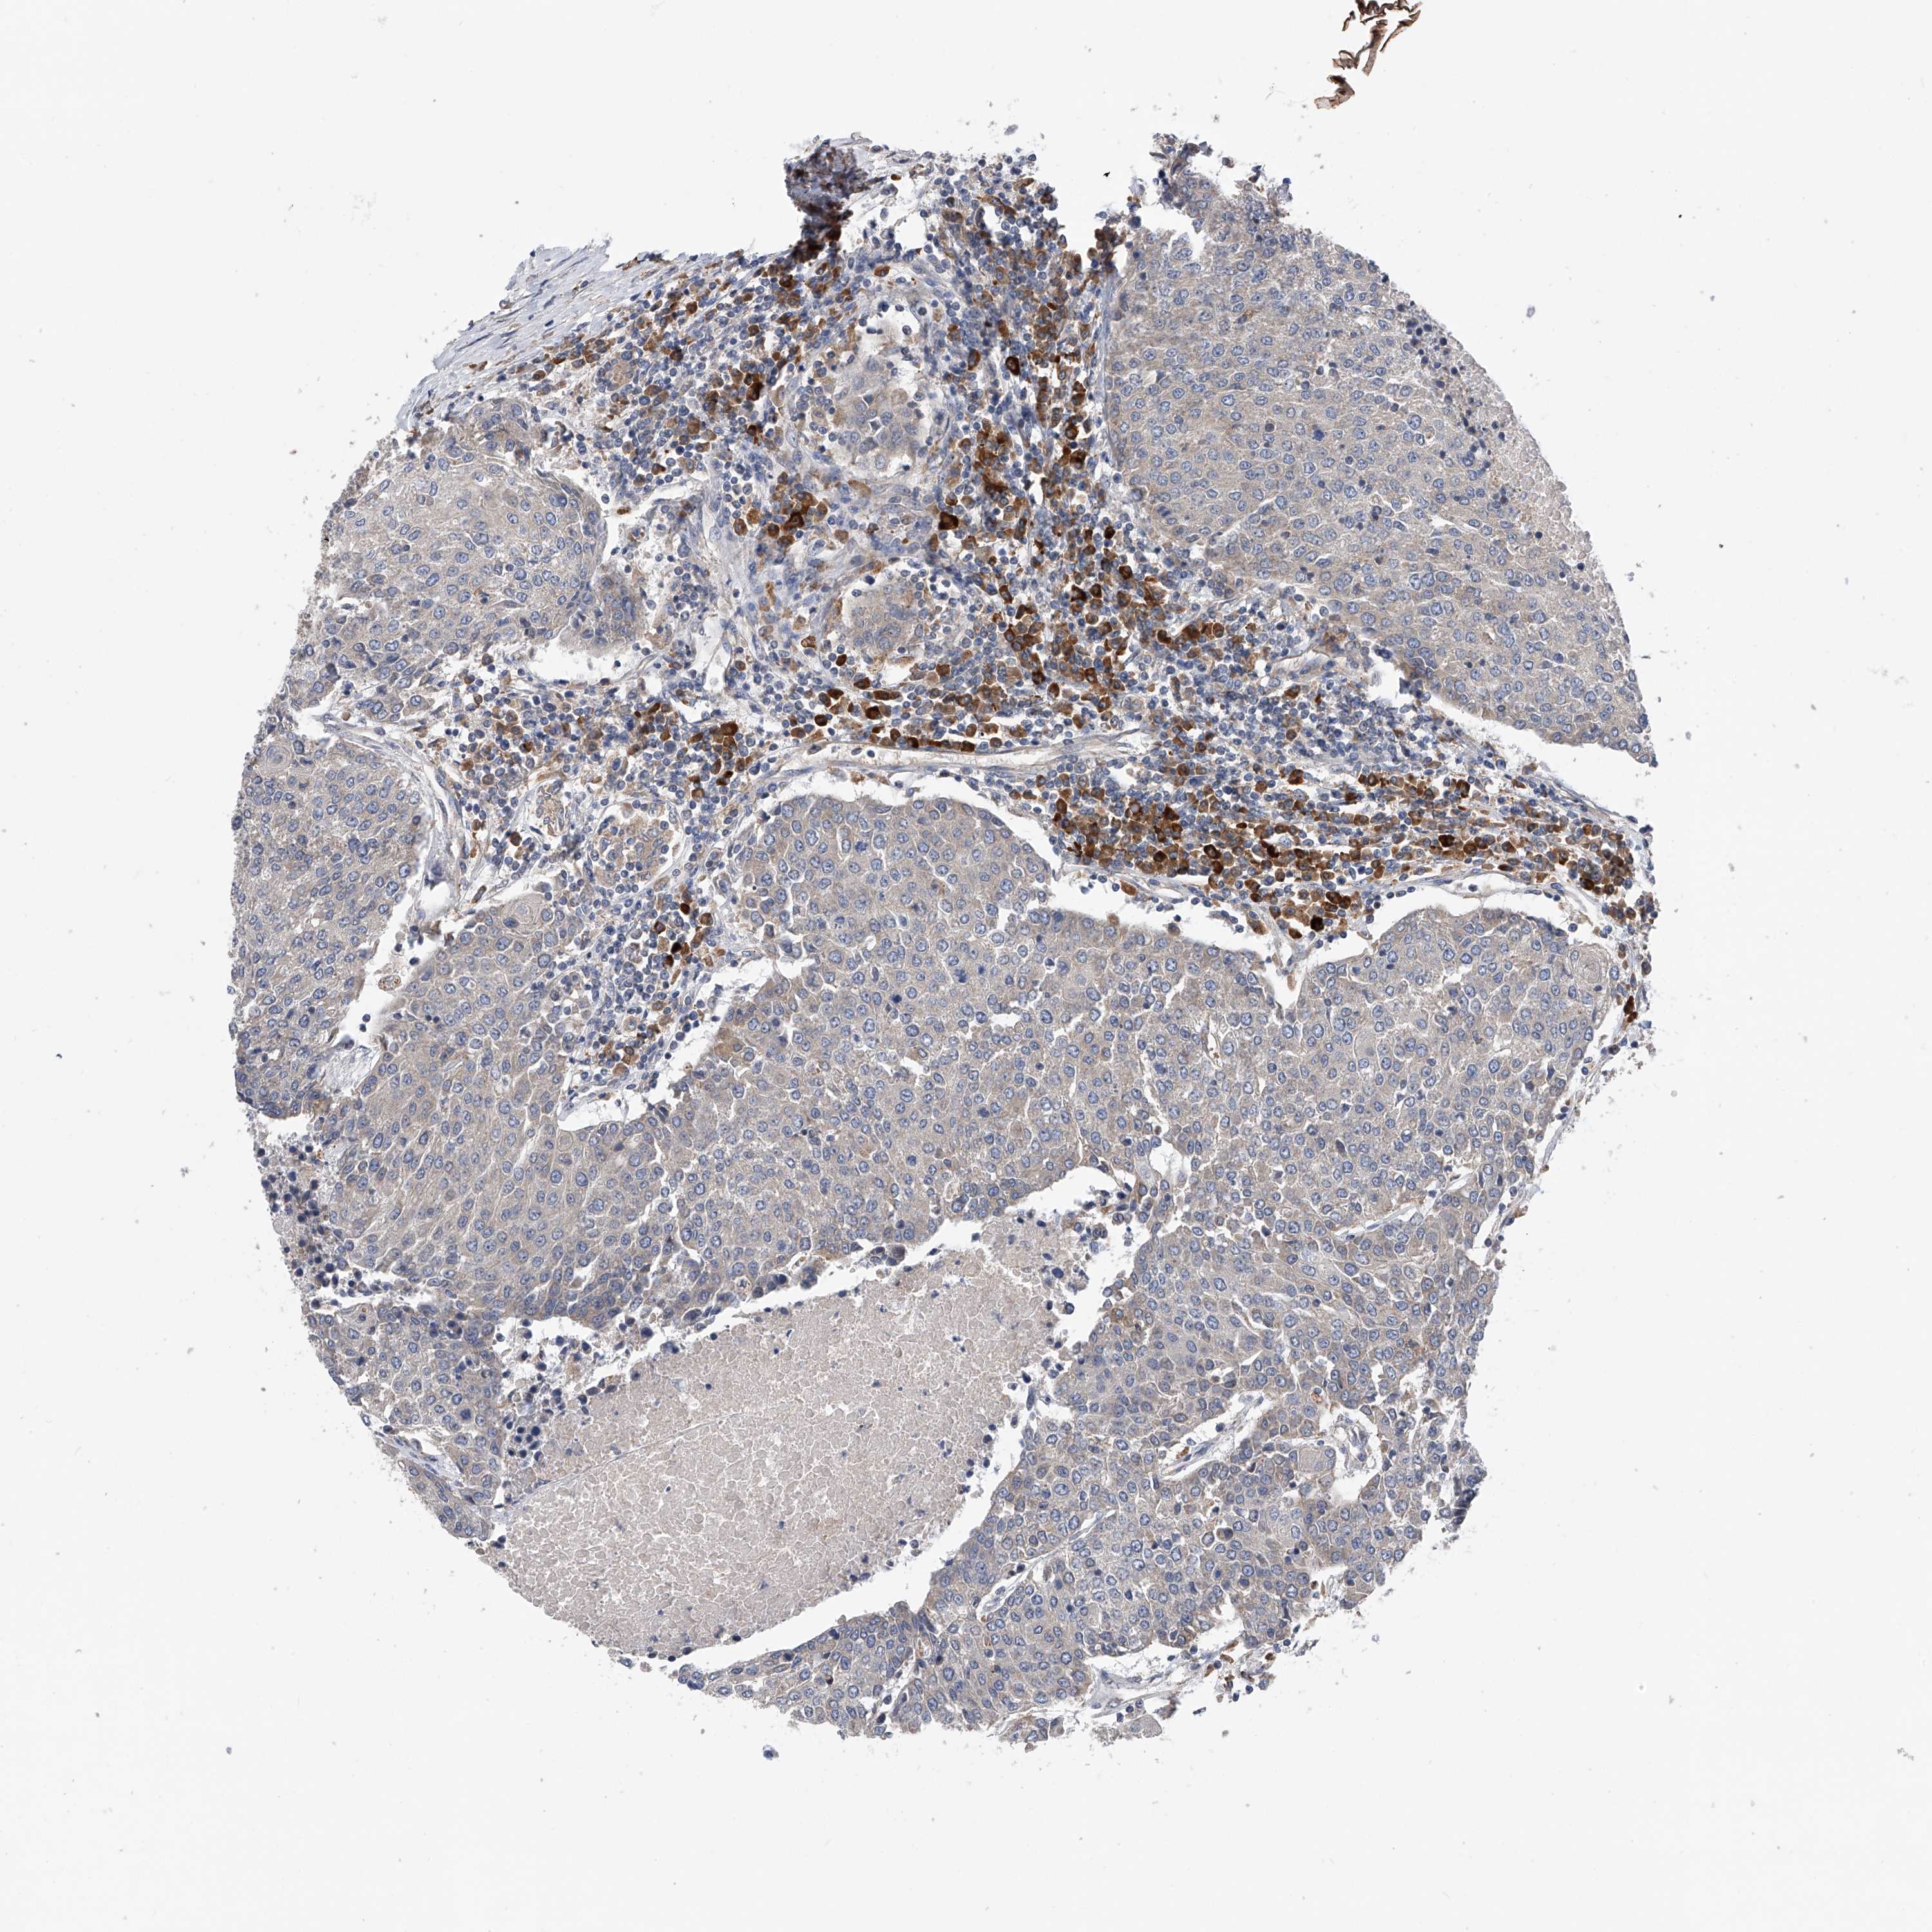

UROTHELIAL CANCER - Protein expressioni

A mouse-over function shows sample information and annotation data. Click on an image to view it in a full screen mode. Samples can be filtered based on level of antibody staining by selecting one or several of the following categories: high, medium, low and not detected. The assay and annotation is described here.

Note that samples used for immunohistochemistry by the Human Protein Atlas do not correspond to samples in the TCGA dataset.

Antibody stainingi

Antibody staining in the annotated cell types in the current human tissue is reported as not detected, low, medium, or high, based on conventional immunohistochemistry profiling in selected tissues. This score is based on the combination of the staining intensity and fraction of stained cells.

Each image is clickable and will lead to virtual microscopy that enables deeper exploration of all samples and also displays staining intensity scores, fraction scores and subcellular localization as well as patient and tissue information for each sample.

Antibody HPA007450

Staining

High

Medium

Low

Not detected

Intensity

Strong

Moderate

Weak

Negative

Quantity

>75%

75%-25%

<25%

None

Location

Nuclear

Cytoplasmic/membranous

Cytoplasmic/membranous,nuclear

Urothelial carcinoma, Low grade

Urothelial carcinoma, High grade